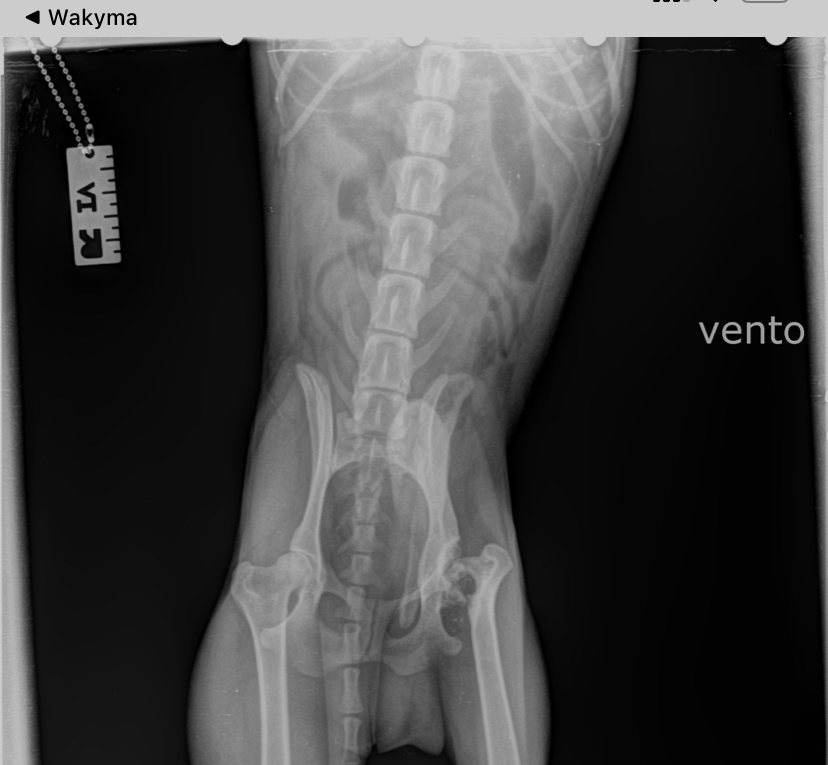

Vento wurde heute kastriert. Da uns aufgefallen war, dass er hinten links hinkt und schont, wurde während der Narkose geröntgt. Diagnose: Er hat eine alte Verletzung am Oberschenkelkopf, die degeneriert ist und zu Lahmheit, Gelenkschmerzen und Verlust von Muskelmasse führt. Exzisionsarthroplastik wird empfohlen.